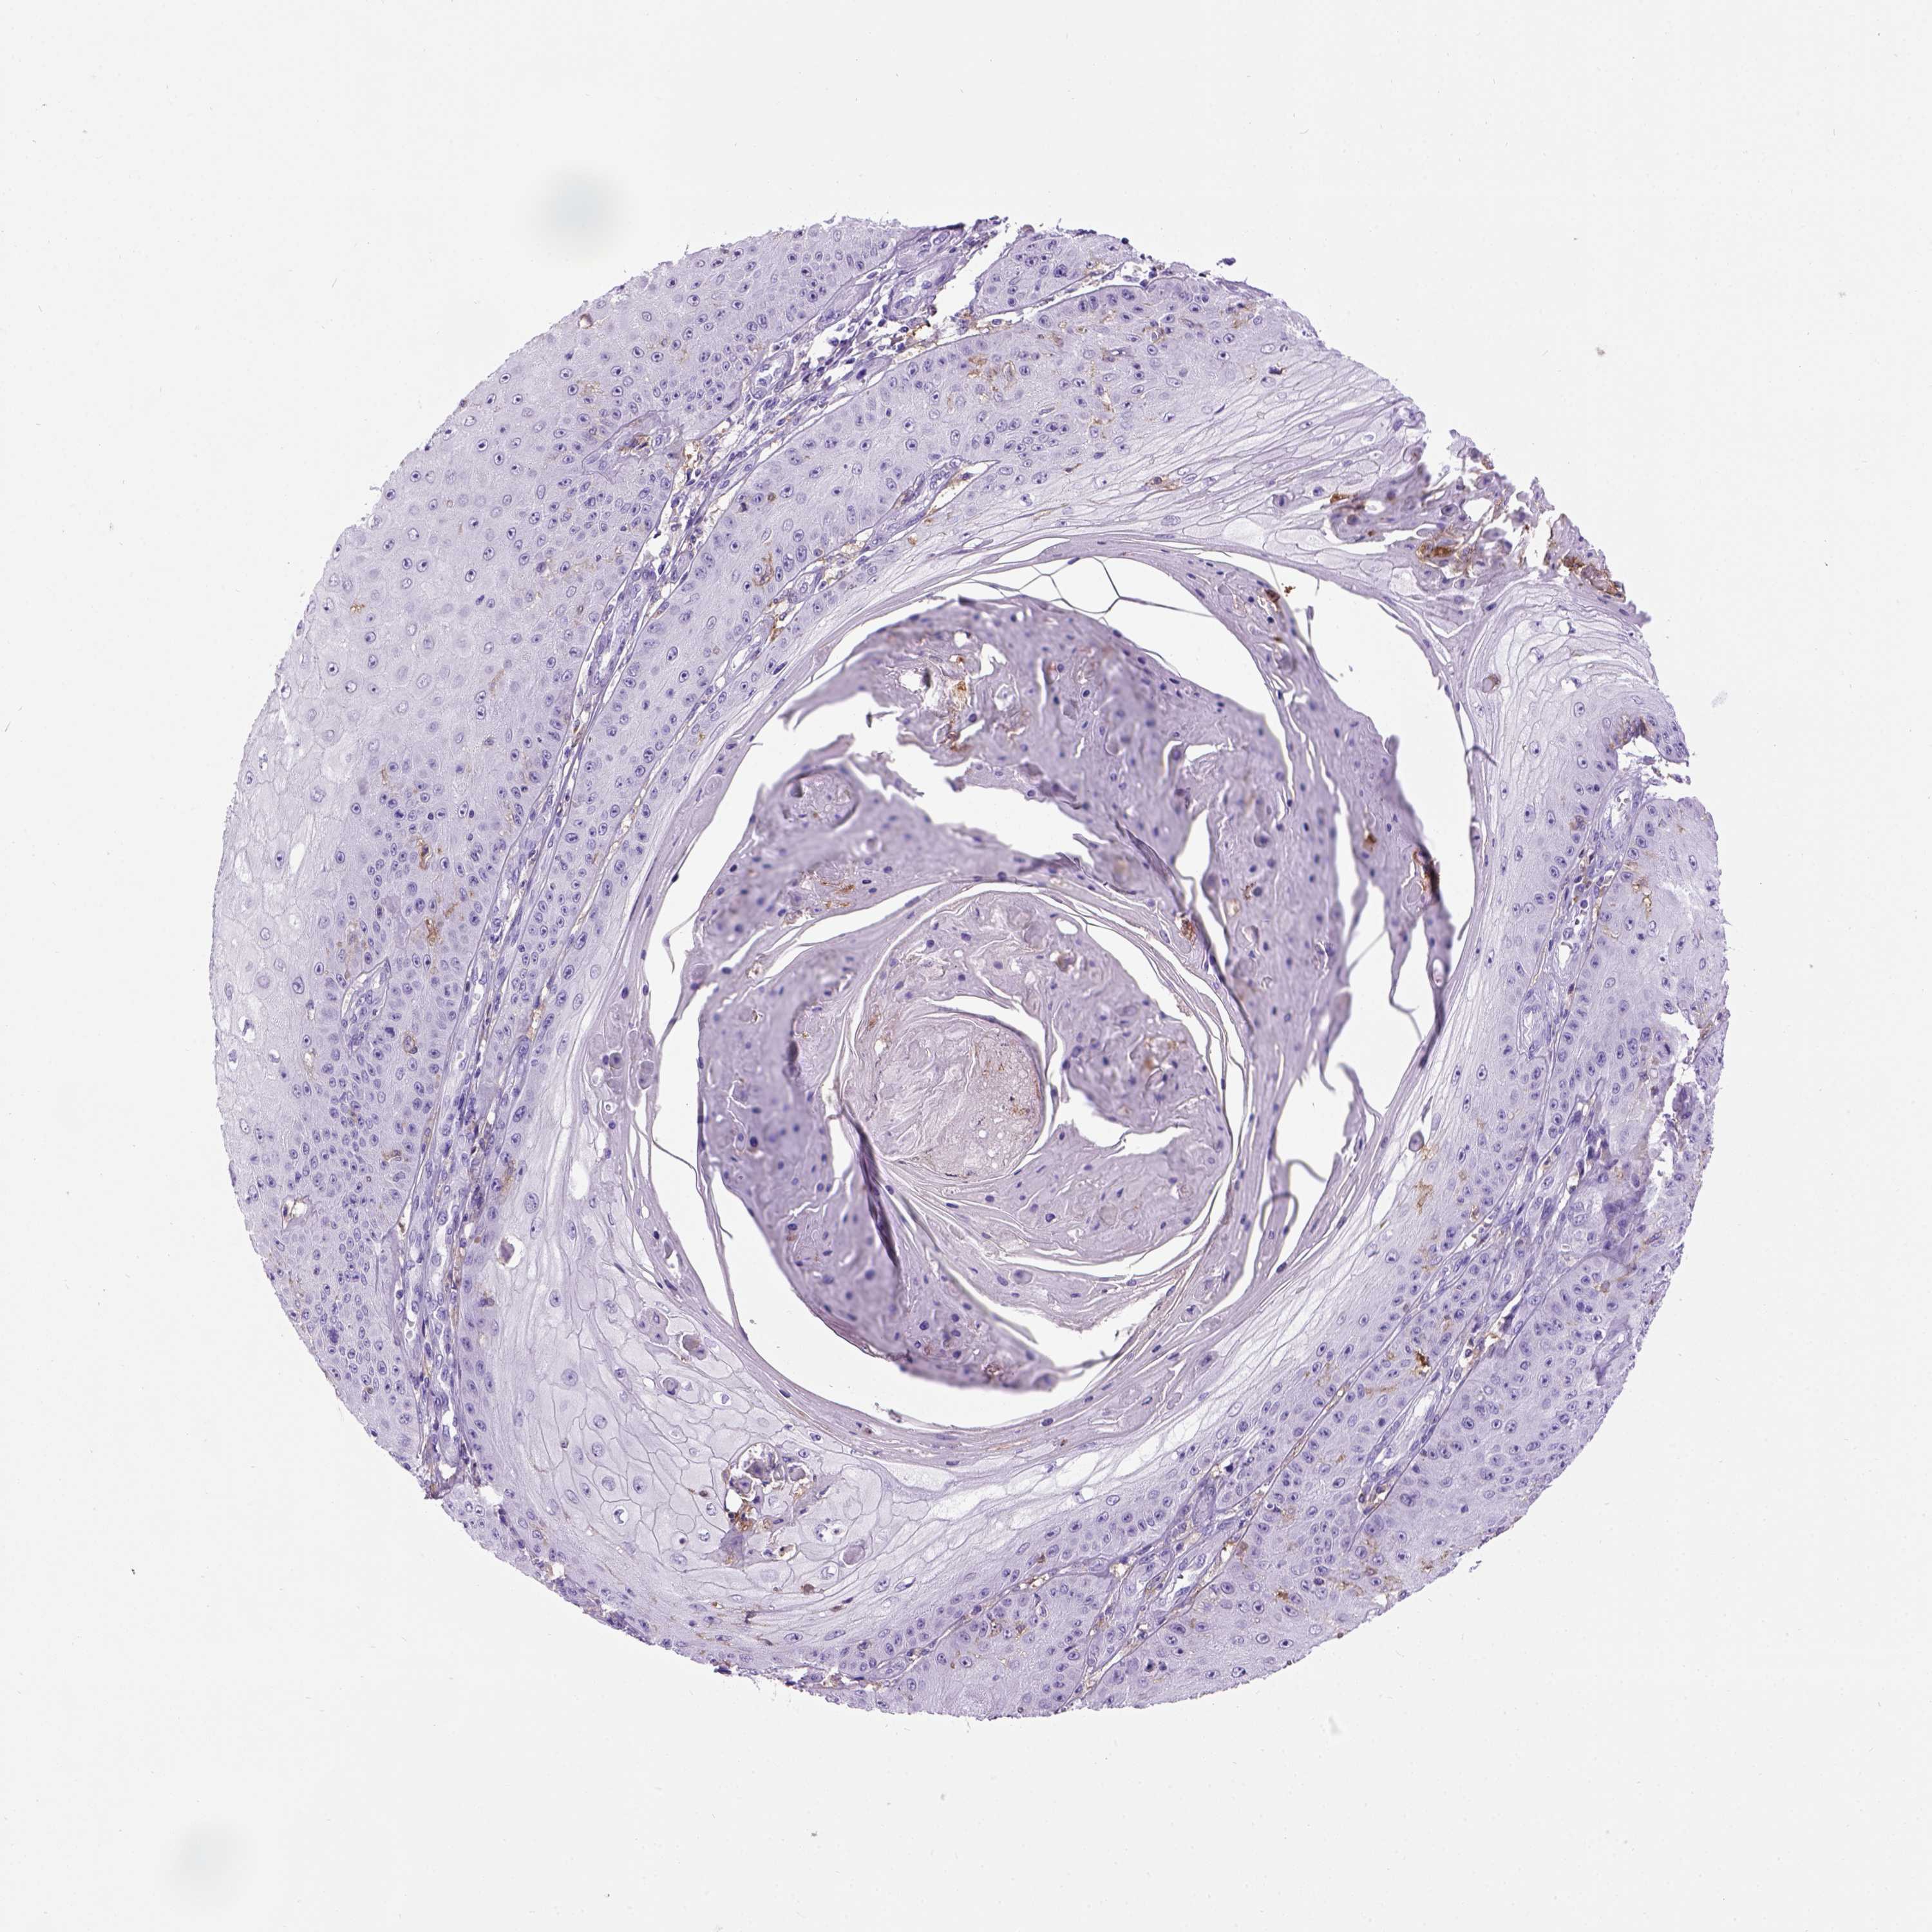

CANCER SKIN CANCER Show tissue menu

Basal cell and squamous cell cancer

SKIN CANCER - Protein expressioni

A mouse-over function shows sample information and annotation data. Click on an image to view it in a full screen mode. Samples can be filtered based on level of antibody staining by selecting one or several of the following categories: high, medium, low and not detected. The assay and annotation is described here.

Each image is clickable and will lead to virtual microscopy that enables deeper exploration of all samples and also displays staining intensity scores, fraction scores and subcellular localization as well as patient and tissue information for each sample.

Antibody HPA004723

Squamous cell carcinoma, NOS

Basal cell carcinoma